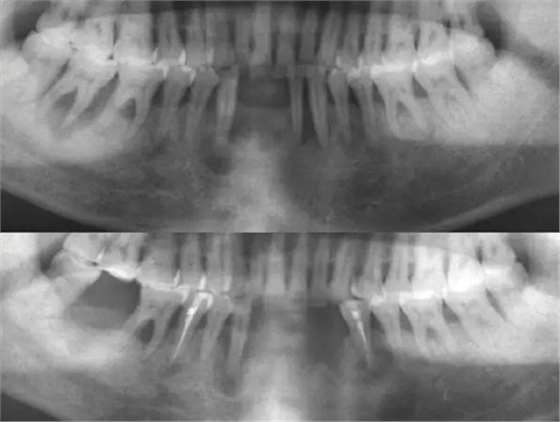

4.通過X線片對(duì)根管系統(tǒng)進(jìn)行預(yù)測(cè)

通過X線片對(duì)根管系統(tǒng)進(jìn)行預(yù)測(cè):確定根管的彎曲度、根管的數(shù)目、根尖彎曲的走向,是否有外吸收、內(nèi)吸收、根裂等情況出現(xiàn),這將對(duì)治療方案的確定有很大幫助。